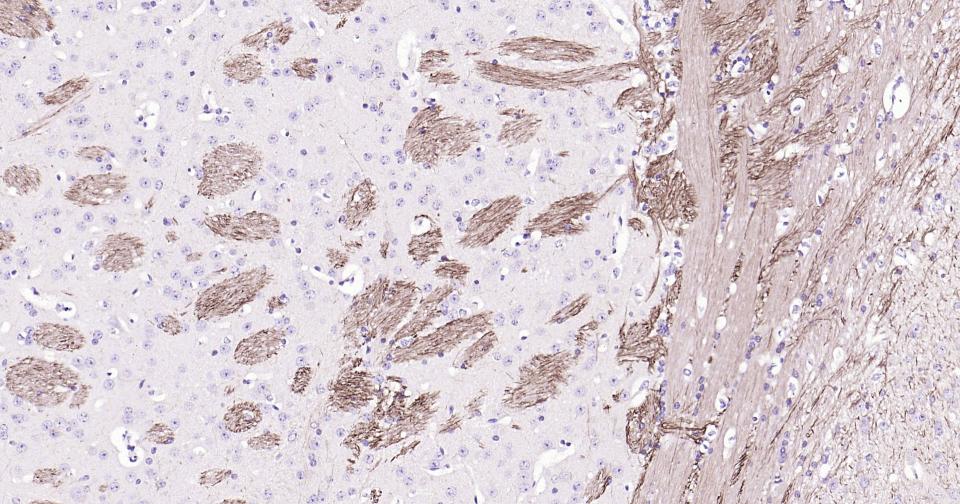

Paraformaldehyde-fixed, paraffin embedded Human Cerebellum; Antigen retrieval by boiling in sodium citrate buffer (pH6.0) for 15 min; Antibody incubation with NEFH Monoclonal Antibody, Unconjugated(bsm-60885R) at 1:200 overnight at 4°C, followed by conjugation to the SP Kit (Rabbit, SP-0023) and DAB (C-0010) staining.